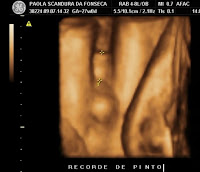

Quanto aos bebês, está tudo ótimo! E parece que realmente chegaremos em 34 semanas facilmente, e não deve haver nenhum motivo de nascerem antes, o que é excelente, esta era nossa meta desde sempre!!!